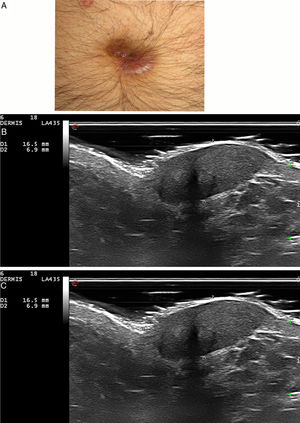

Se incluyó a 5pacientes (4 hombres y una mujer) con 6lesiones en total, con una mediana de edad de 67 años (rango: 39-71) y una biopsia comprobada de granuloma facial. En 3pacientes las lesiones estaban localizadas en la cara, en uno en el cuero cabelludo, en otro en la oreja y en otro en el ombligo. La mayoría de los pacientes habían sido tratados mediante diferentes tratamientos sin obtener mejoría clínica (tabla 1). En la evaluación ecográfica, el granuloma facial se presentó como una lesión hipoecoica y heterogénea situada en la dermis e hipodermis con un aumento de la vascularización en el modo color Doppler (figs. 1-2). Casi todas las lesiones (5/6) estaban mal definidas. En 5 de los granulomas faciales se observó una banda hipoecoica/anecoica subepidérmica marcada. Una lesión (caso 5, nariz) presentó un refuerzo posterior. No hubo diferencias significativas en las características ecográficas entre los granuloma facial faciales y extrafaciales (tabla 1).

| 3 | H/67 | 12 | OrejaOmbligo | Corticosteroides tópicos e intralesionales, tacrolimus tópico, hidroxicloroquinaCorticosteroides tópicos e intralesionales, tacrolimus tópico, hidroxicloroquina | Presencia de zona de GrenzInfiltrados inflamatorios linfoplasmocíticos densos en la dermisPresencia de zona de GrenzInfiltrados inflamatorios linfoplasmocíticos densos en la dermis | Lesión hipoecoica, heterogénea y mal definida en dermis e hipodermisLesión hipoecoica, heterogénea y bien definida en dermis e hipodermisBanda subepidérmica hipoecoica | Aumento de la vascularizaciónVasos en la dermis con un diámetro superior a 0,8mmAumento de la vascularizaciónVasos en la dermis con un diámetro superior a 1,4 mm |